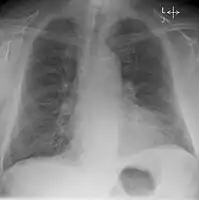

Chest X-ray

Chest X-rays are frequently used to aid in the diagnosis of CHF. In a person who is compensated, this may show cardiomegaly (visible enlargement of the heart), quantified as the cardiothoracic ratio (proportion of the heart size to the chest). In left ventricular failure, there may be evidence of vascular redistribution ("upper lobe blood diversion" or "cephalization"), Kerley lines, cuffing of the areas around the bronchi, and interstitial edema. Ultrasound of the lung may also be able to detect Kerley lines.[39]

Congestive heart failure with small bilateral effusions.

Kerley b lines.